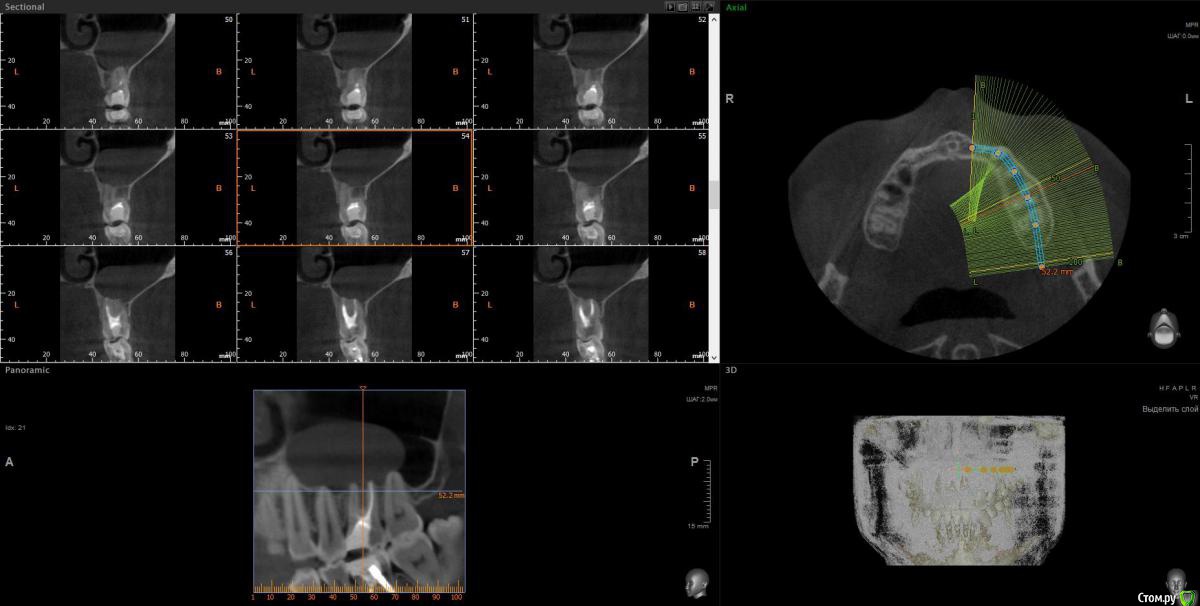

wladdX Опубликовано 13 декабря, 2016 Поделиться Опубликовано 13 декабря, 2016 Несколько скриншотов. Ссылка на комментарий